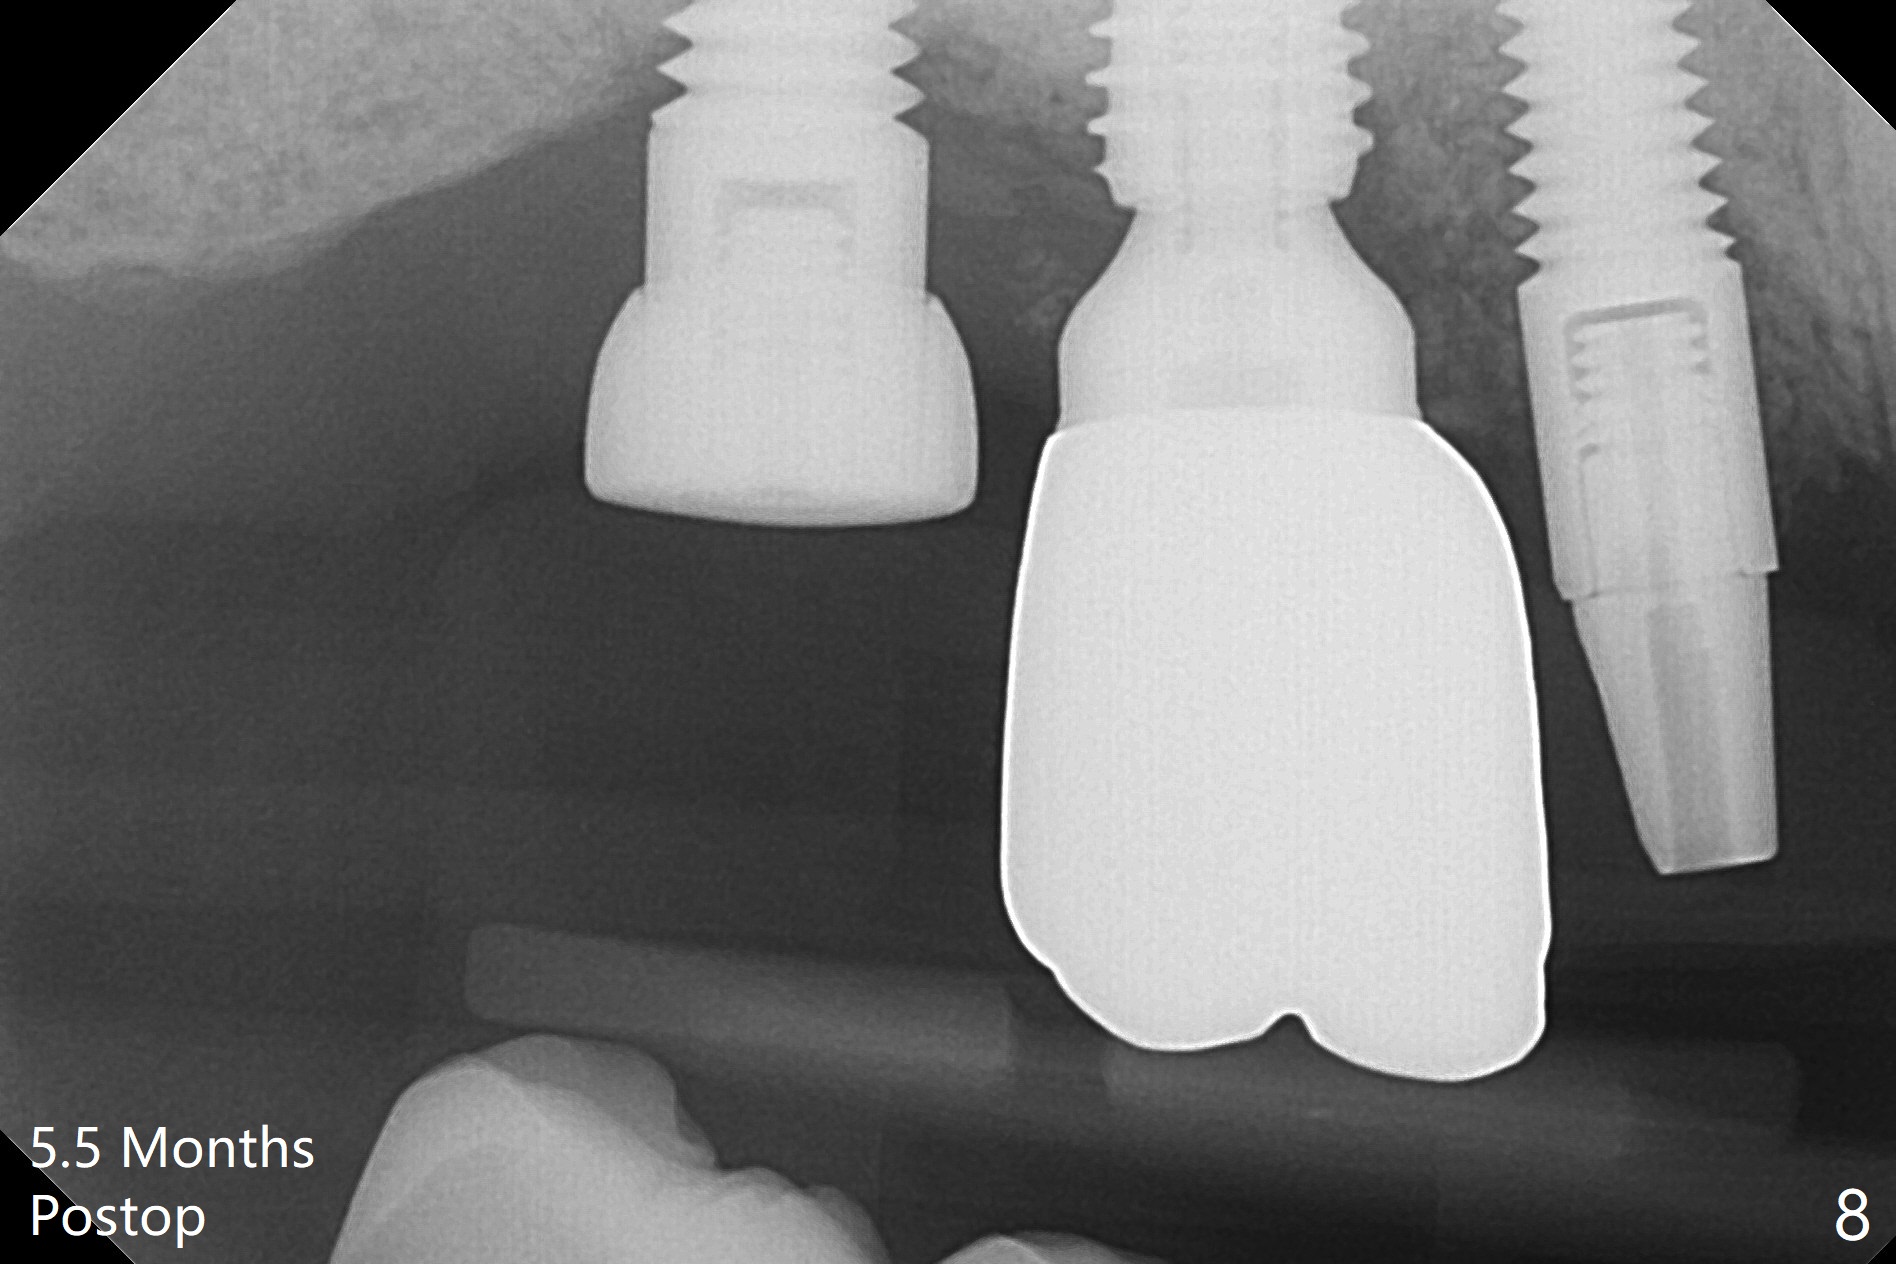

After osteotomy using bone-level implant guide at #4, the crown and abutment at #3 has to be removed to place a 4x14 mm tissue-level dummy implant because of the narrow space of #4 and implant placement angulation (Fig.1). Following initial placement of a final 4x17 mm implant and bone graft (Fig.2 *), the crown and abutment of #3 and the guide are reseated for correct implant trajectory. The guide has to be removed for final depth control. With the same mode, a 5x17 mm tissue-level tap is used at #2 following bone-level osteotomy with guide. A 5x14 mm tissue-level implant is placed with >50 Ncm (later placed deeper), while more bone graft is inserted mesial of #4 implant with a 3.5x5 mm abutment (Fig.3 *). Bone graft is introduced into the sinus using guided sinus lift kit (Fig.4,5 (CT sagittal and coronal sections)) * (D: distal, P: palatal)). The coronal half of the implant at #4 is covered by bone graft (Fig.6 *) buccal (B) and palatal within the deep socket. The implants at #2 and 4 seem to have osteointegrated nearly 5.5 months postop (Fig.7,8 (BW)). A 4.5x5 mm unipost is later placed at #2 with long chamfer margin. It appears that the abutment at #3 is wide. The hex is worn. It changes to a 5.5x7(4) mm one. After abutment adjustment for parallelism, a provisional FPD is fabricated. The latter will be adjusted for papilla formation between implants to reduce food impaction.